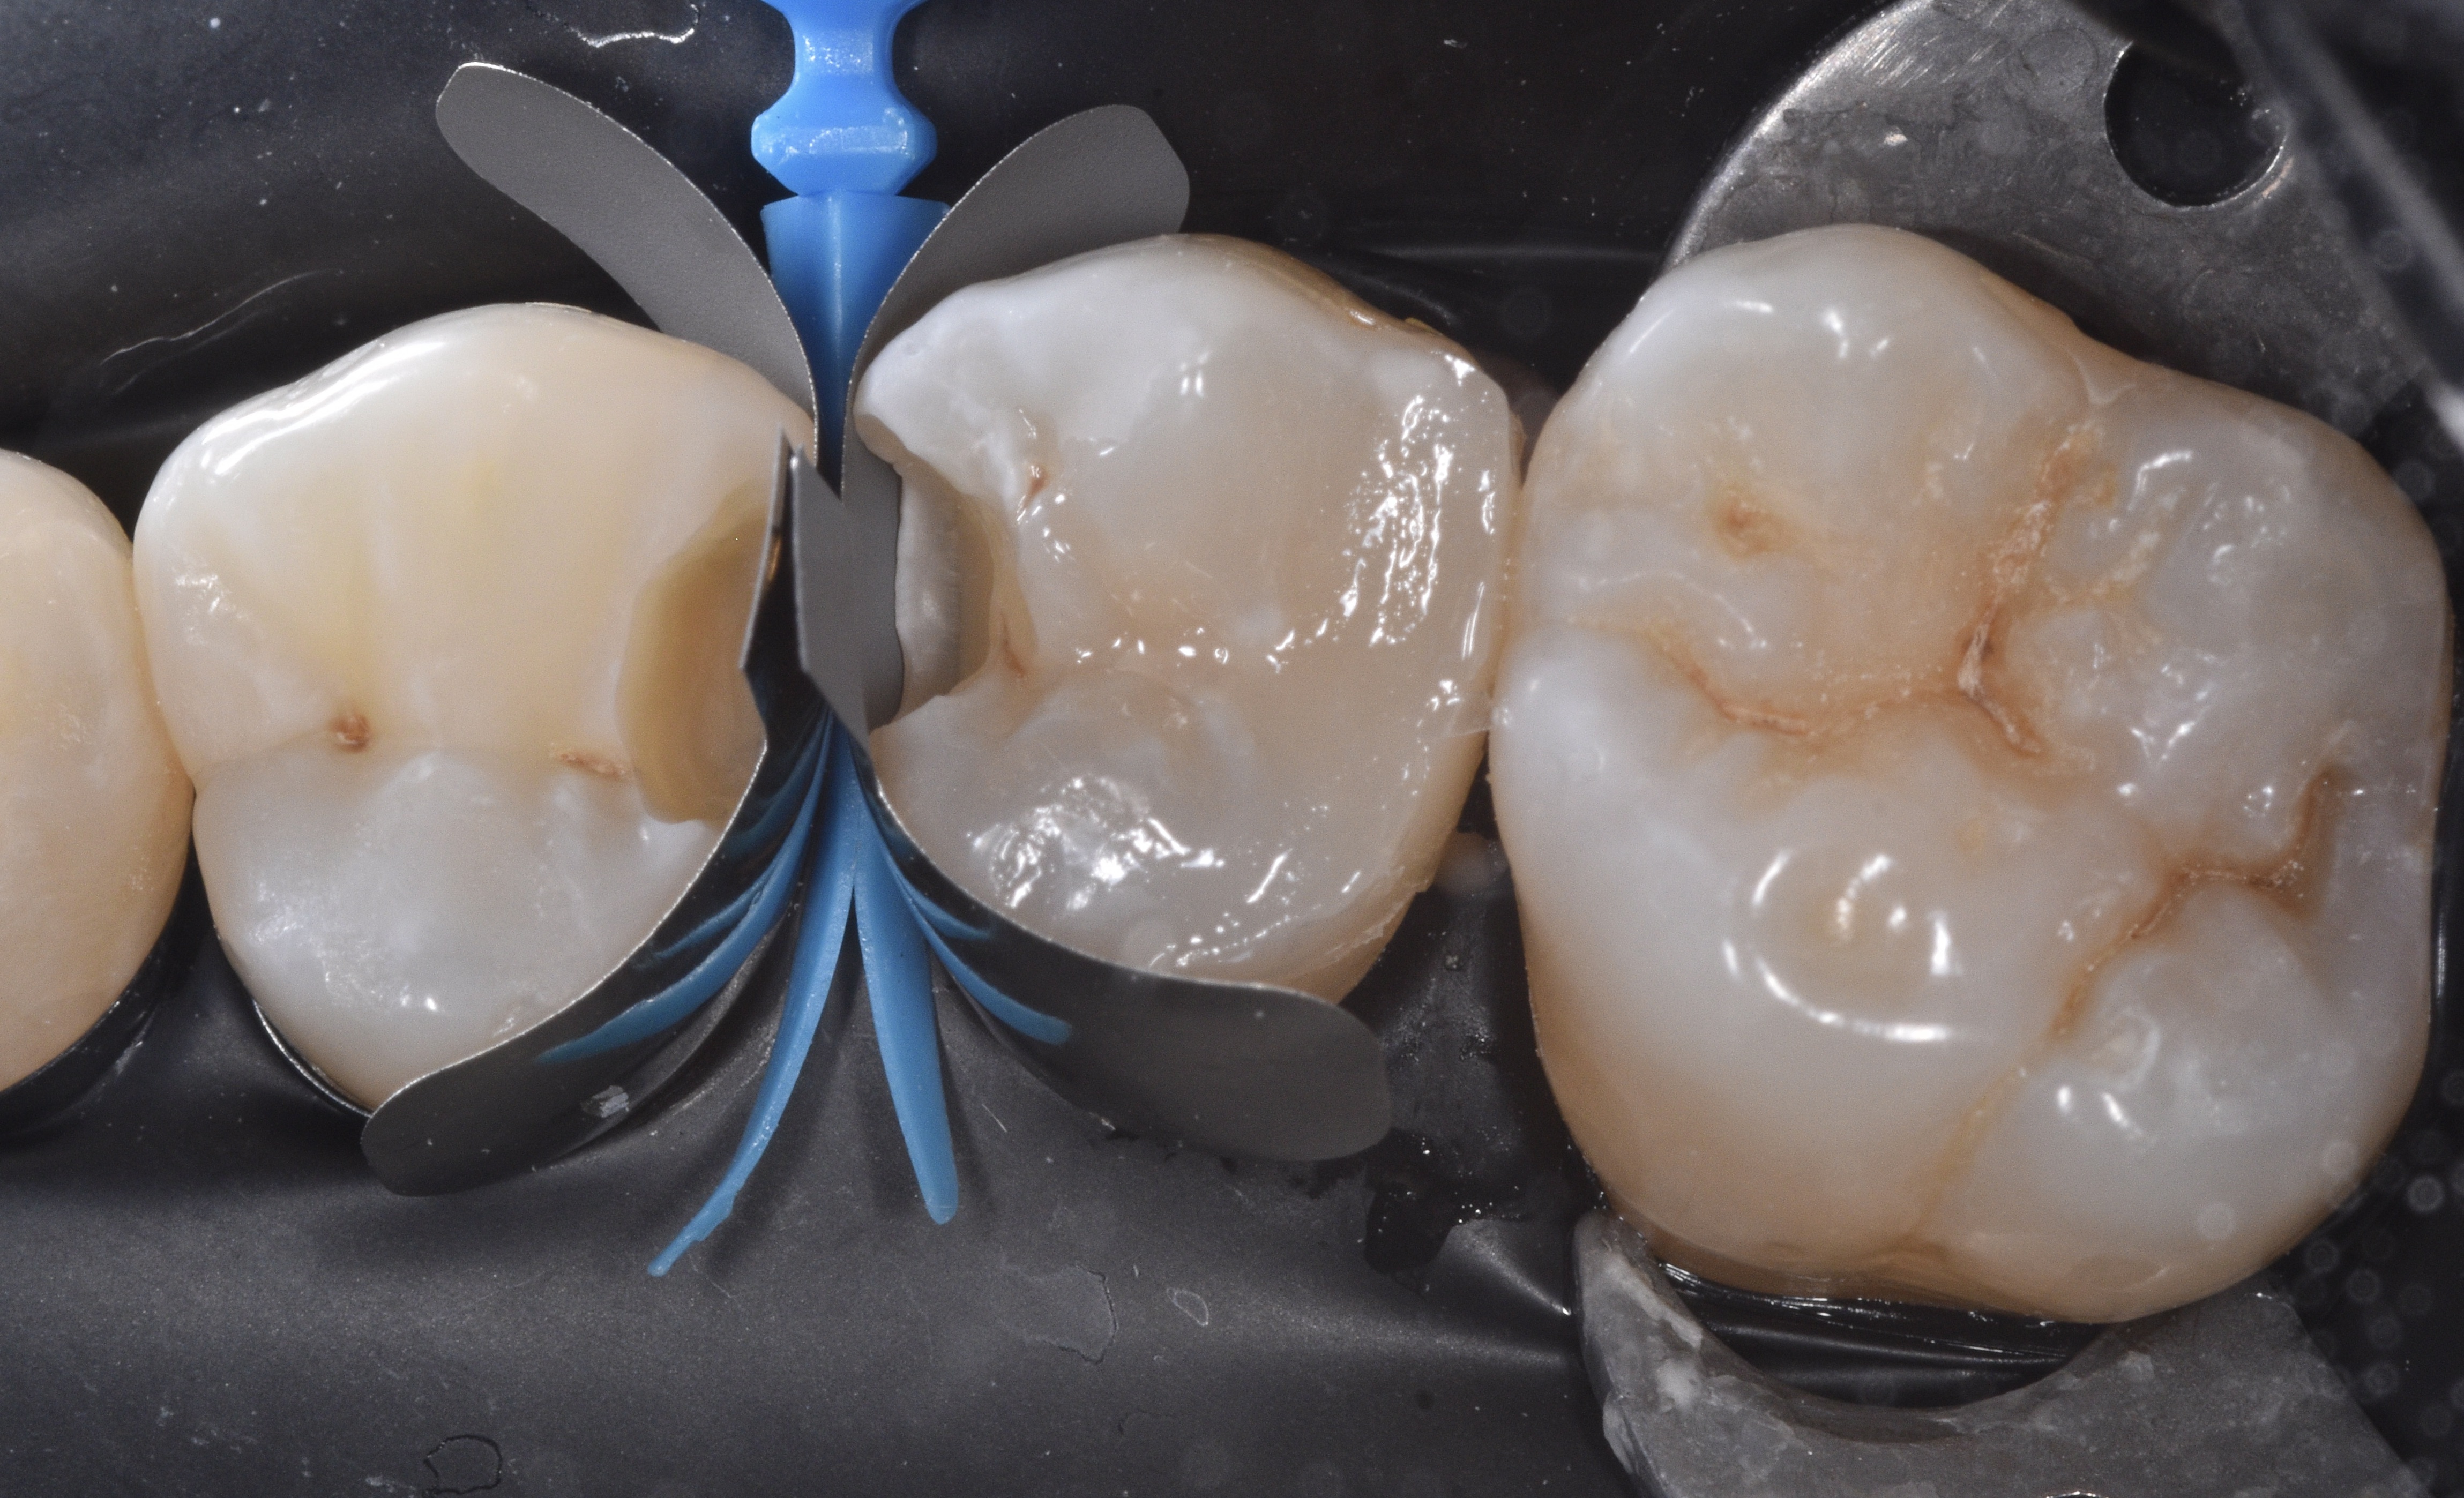

Caries was removed using a minimal intervention approach which helped with keeping the central groove area intact on tooth #13 (Figure 2). Once the infected dentin was completely removed and a clean peripheral seal zone obtained, we cleaned the preparations using 23-micron aluminum oxide combined with distilled water (AquaCare) and then moved forward with selecting the ideal matrix system for this case. Garrsion’s Quad matrix system has quickly become my preferred due to its “split” wedge systems that helps with “pushing” the band mesial, distal or both (in back-to-back cases) (Figure 3).

Figure 3

Figure 2Figure 3

We remove the sectional matrix system and place it in between teeth #12-13 to restore both preparations simultaneously (Figure 7). See how the Quad wedge split tip contours the bands even prior to placing the ring.

Figure 7

Make sure that the black arrow is always placed towards the lingual and that it pushes each end of the split wedge towards the mesial and distal as seen on Figure 8